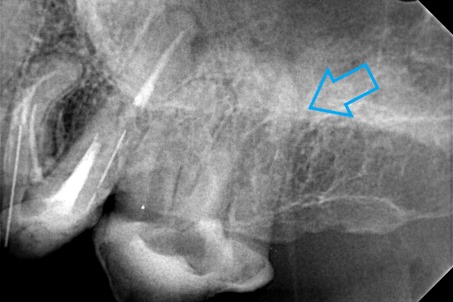

Ο ασθενής πονούσε πολύ στον άνω γομφίο, που είχε απονευρωθεί πριν από χρόνια. Αποφασίστηκε η επανάληψη απονεύρωσης του δοντιού, κατά την οποία διαπιστώθηκε οτι υπήρχε και τέταρτος ριζικός σωλήνας που δεν είχε βρεθεί και επεξεργαστεί κατά την πρώτη προσπάθεια απονεύρωσης. Πλέον το δόντι είναι ασυμπτωματικό.

Παλιά απονεύρωση του δύο άνω γομφίου

Νέα απονεύρωση στον άνω γομφίο